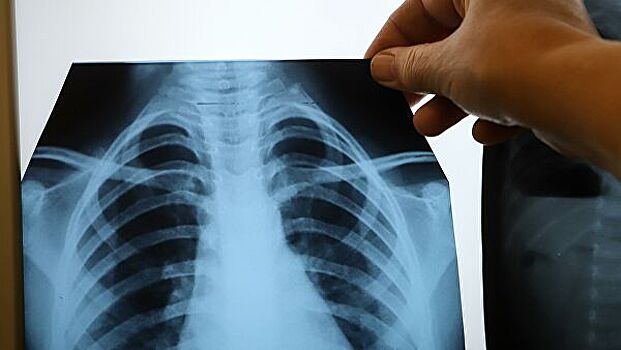

Ученые назвали витамин, способствующий подавлению клеток рака легких

Ученые Московского государственного университета имени М.В. Ломоносова обнаружили, что лекарственная форма витамина В1 - кокарбоксилаза - в высоких дозах может оказывать негативное воздействие на клетки рака легких, не затрагивая при этом здоровые, сообщает пресс-служба МГУ.

Рак легкого — один из наиболее тяжело поддающихся лечению типов рака, который занимает первое место по летальности среди больных.